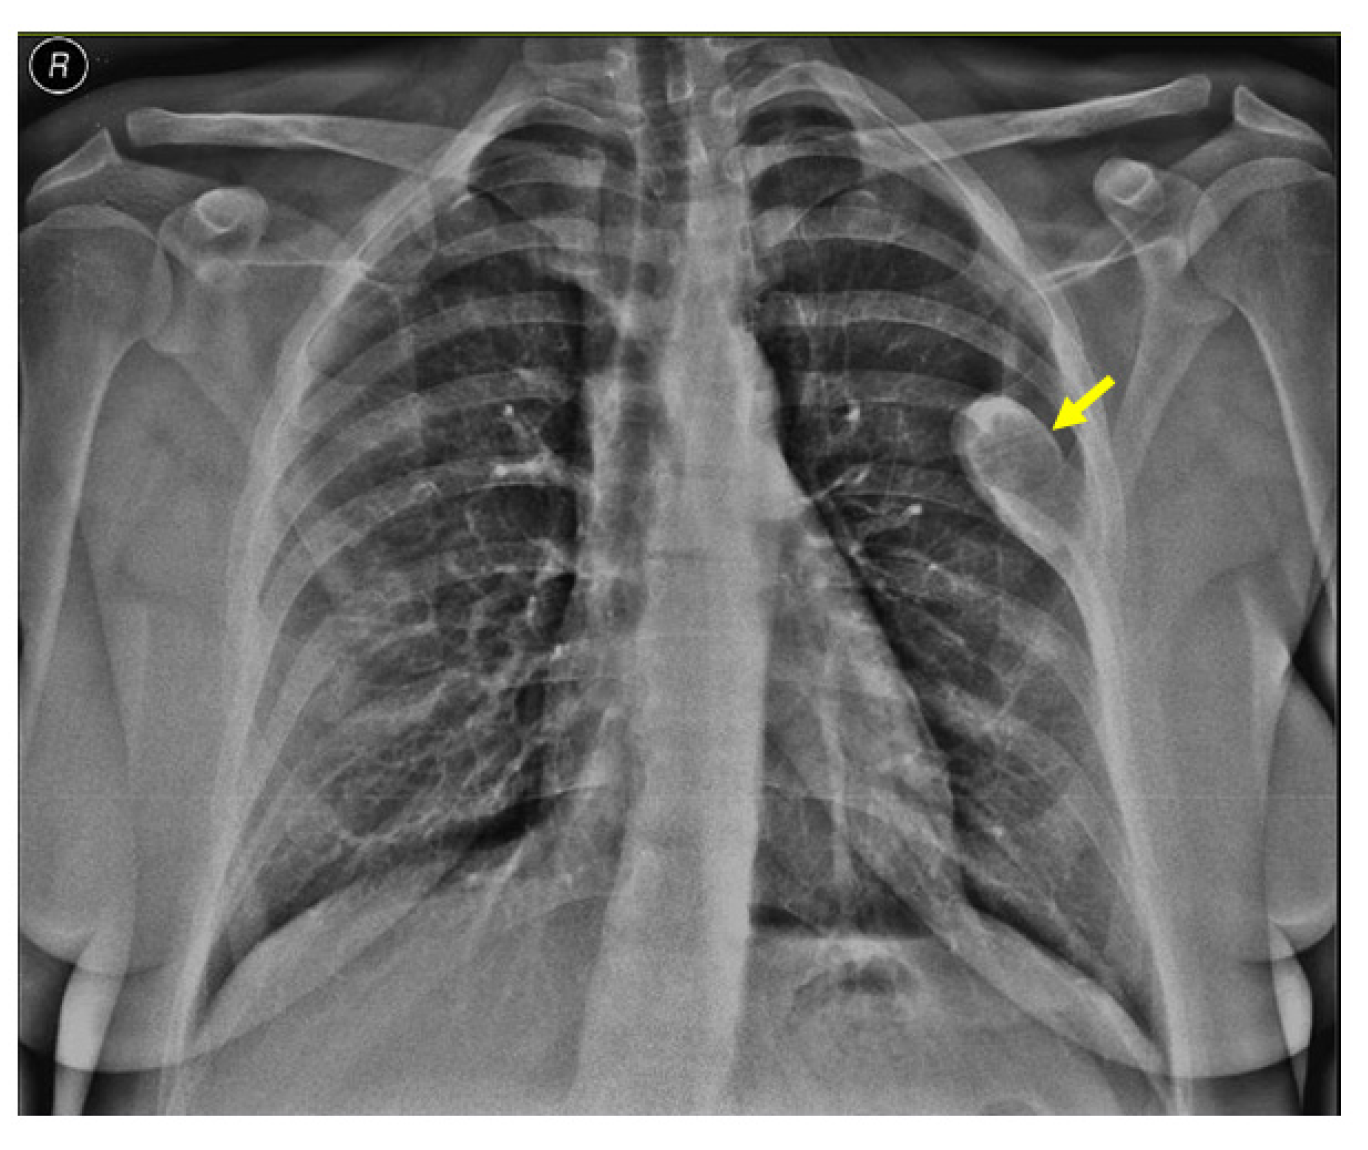

Noting the bone pain on admission, an X-ray screening was performed and showed a rib tumor suggestive of a brown tumor (a solitary, oval, well-shaped tumor of 6.4 by 2.7 cm in the lateral half of the left posterior sixth rib) (Figure 3).

Figure 3.

X-ray showing a brown tumor: a single, oval, well-shaped lesion of 6.4 by 2.7 cm in the lateral half of the left posterior sixth rib (yellow arrow).

An X-ray of the pelvis also revealed multiple osteolytic lesions of the ischium (brown tumor features) with normal femoral head sphericity and position and a mildly reduced coxo-femoral joint space (Figure 4).

Figure 4.

X-ray of the pelvis: brown tumors at the level of the ischium (yellow arrows).